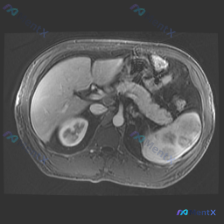

看到一份很有意思的影像读片案例,用户的问题聚焦在“脾脏病变”,但影像本身却给了我们一个完全不同的方向,整理一下思路和大家分享。 --- 先看影像基本情况 - 序列:腹部MRI T2加权轴位像 - 用户焦点:脾脏病变 关键影像发现(按实际读片顺序) 1. 肝脏、胆囊、胰腺:未见明显异常信号或肿块,胆管...